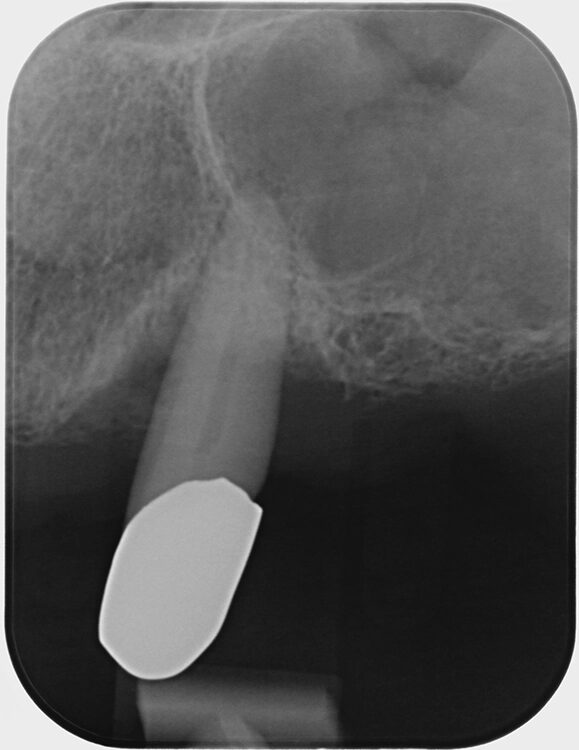

Abb. 3 a–e: Klinische Dokumentation eines 63-jahrigen männlichen Patienten (geb. 05.09.1961). Die Fotodokumentation erfolgte erst am Tag der AIT und nicht im Rahmen der klinischen und radiologischen und 47 wurden vor der AIT entfernt. An den Zahnen 13 und 23 war neben der peniblen subgingivalen Instrumentierung die Applikation von Straumann® Emdogain® (Straumann Group, Basel, Schweiz) vorgesehen.Walter

Abb. 3 a–e: Klinische Dokumentation eines 63-jahrigen männlichen Patienten (geb. 05.09.1961). Die Fotodokumentation erfolgte erst am Tag der AIT und nicht im Rahmen der klinischen und radiologischen und 47 wurden vor der AIT entfernt. An den Zahnen 13 und 23 war neben der peniblen subgingivalen Instrumentierung die Applikation von Straumann® Emdogain® (Straumann Group, Basel, Schweiz) vorgesehen.

Abb. 3f: Ausschnitt aus der Panoramaschichtaufnahme des in Abb. 3a-e dargestellten Patientenfalles. Deutlich wird der weit fortgeschrittene Attachmentverlust an nahezu allen Zähnen. Die ausgeprägte vertikale Komponente ist günstig für erfolgversprechende die Regeneration fördernde Maßnahmen.Walter

Abb. 3f: Ausschnitt aus der Panoramaschichtaufnahme des in Abb. 3a-e dargestellten Patientenfalles. Deutlich wird der weit fortgeschrittene Attachmentverlust an nahezu allen Zähnen. Die ausgeprägte vertikale Komponente ist günstig für erfolgversprechende die Regeneration fördernde Maßnahmen.

Es handelt sich hierbei um einen 63-jährigen männlichen Patienten (geb. 05.09.1961). Allgemeinmedizinisch war eine rheumatoide Erkrankung und die Einnahme von Methotrexat (Folsäureantagonist, Zytostatikum und Immunsuppressivum) dokumentiert. Etwaige orale Nebenwirkungen dieser Medikation lagen nicht vor. Herr B. war Nichtraucher. Der Patient wünschte maximalen Zahnerhalt und wurde daher zur parodontalen Therapie der bereits weit fortgeschrittenen Parodontitis an eine spezialisierte Praxis überwiesen. Zu diesem Zeitpunkt waren im Oberkiefer noch 2 und im Unterkiefer noch 5 Zähne vorhanden.

Der parodontale Screening-Index (PSI) an den verbliebenen Zähnen zeigte erhöhte Zahnlockerungen, stark entzündete und blutende Areale sowie Sondierungstiefen weit über 5 mm hinaus. Es lag dem zufolge ein Code 4* und damit die Notwendigkeit gründlicher Diagnostik vor. Die weiterführenden parodontalen Untersuchungen führten zur Diagnose einer generalisierten Parodontitis Stadium IV Grad C [46]. Die parodontal entzündete Wundfläche betrug 1088,69 mm2 [47]. Radiologisch konnten neben dem generalisierten horizontalen Knochenverlust auch ausgeprägte vertikale Defekte z.B. an den Zähnen 13 und 23 detektiert werden. Darüber hinaus wurde ein Chairside Vitamin-D-Test durchgeführt (Botiss, Straumann Group, Basel, Schweiz). Der Wert betrug 10 ng/ml und bedeutete, dass hier ein schwerer Vitamin-D-Mangel mit entsprechenden Implikationen für den Knochenstoffwechsel vorlag. Dem Patienten wurde eine Vitamin-D-Supplementierung mit zunächst 2000 IE und die Vorstellung bei seinem Hausarzt zu etwaiger weiterer Diagnostik und Festlegung einer optimierten Vitamin-D-Nahrungsergänzung empfohlen [48].